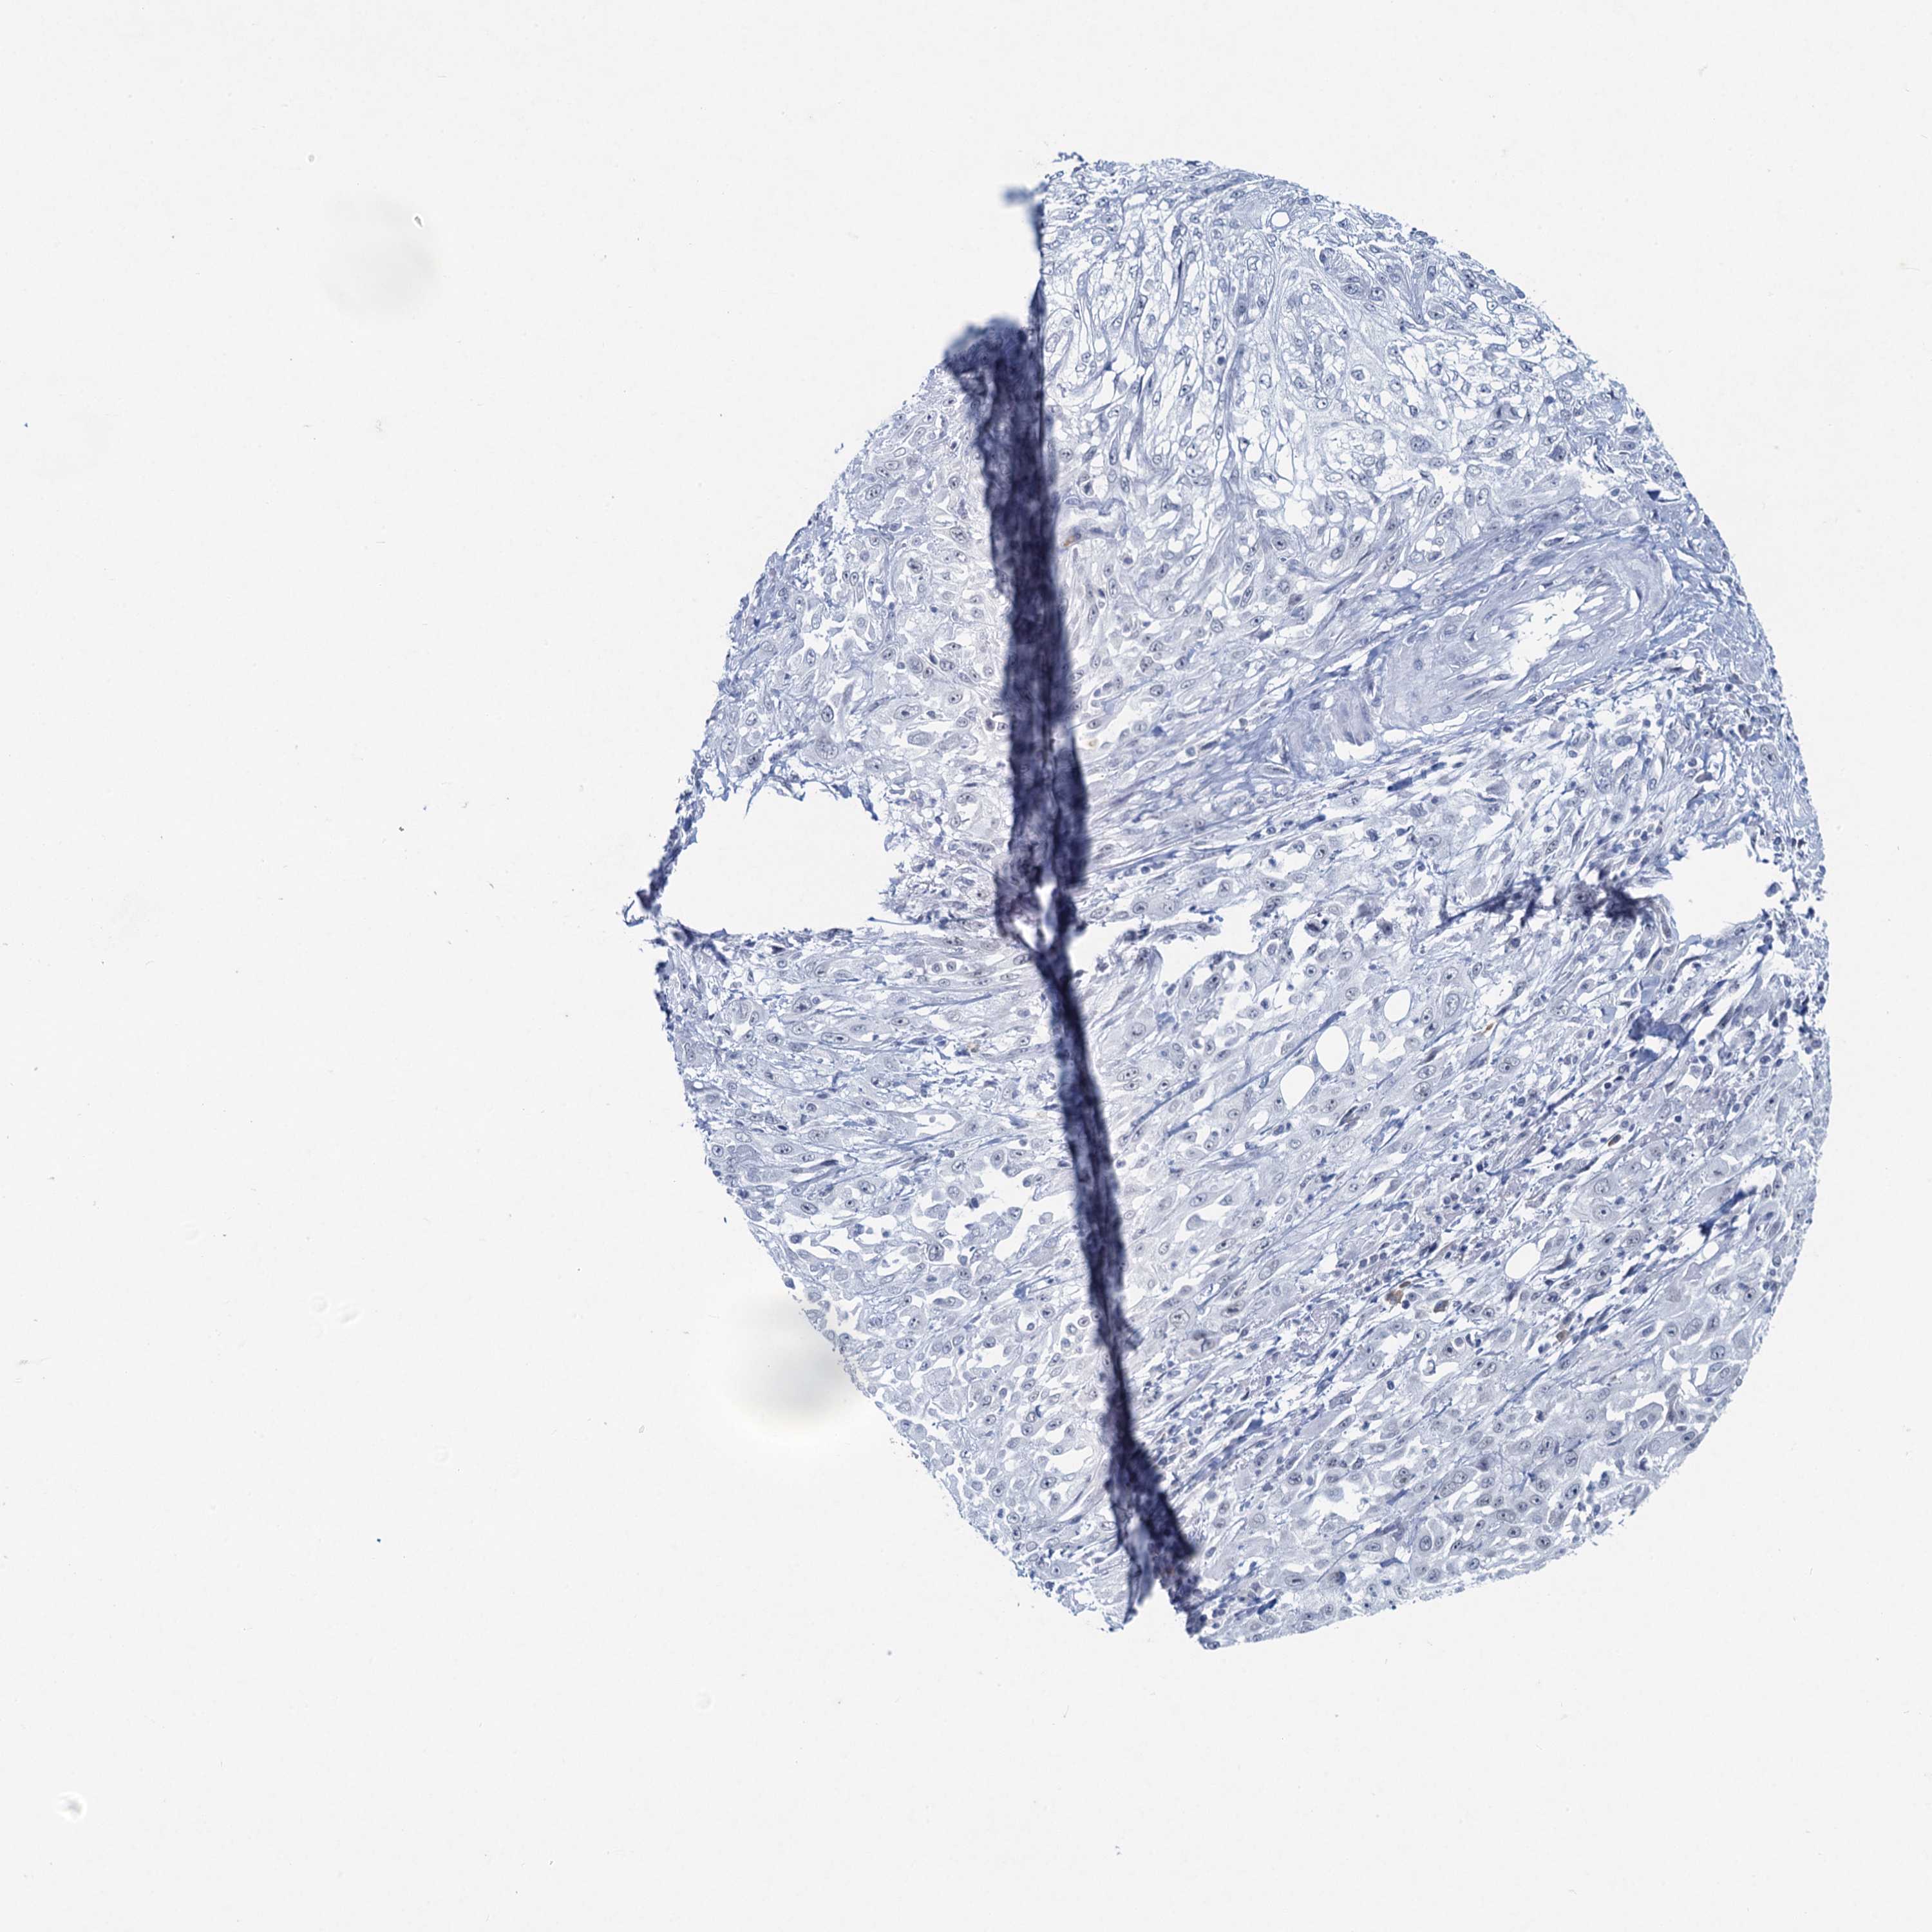

CANCER SKIN CANCER Show tissue menu

Basal cell and squamous cell cancer

SKIN CANCER - Protein expressioni

A mouse-over function shows sample information and annotation data. Click on an image to view it in a full screen mode. Samples can be filtered based on level of antibody staining by selecting one or several of the following categories: high, medium, low and not detected. The assay and annotation is described here.

Each image is clickable and will lead to virtual microscopy that enables deeper exploration of all samples and also displays staining intensity scores, fraction scores and subcellular localization as well as patient and tissue information for each sample.

Antibody HPA041568

Staining

High

Strong

Quantity

Location

Basal cell carcinoma